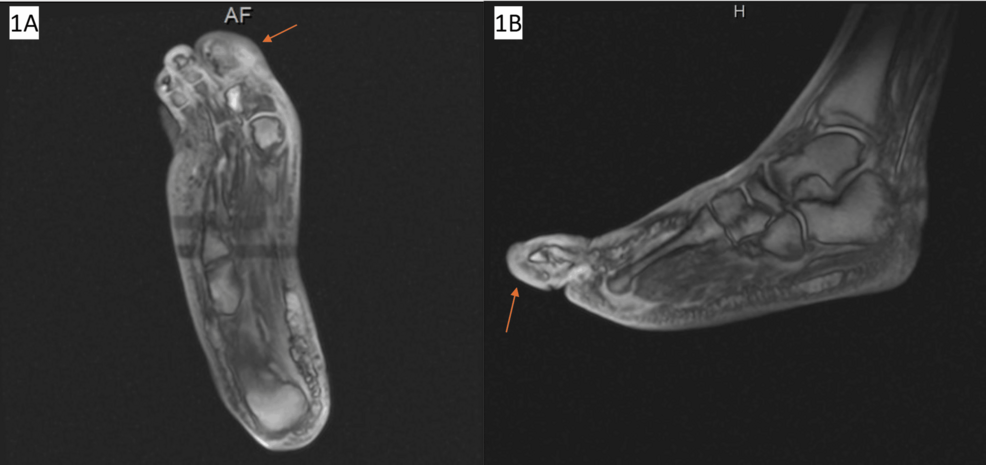

The Patient, suffering from MRSA bacteremia, developed subretinal abscesses, which are pockets of infection beneath the retina. This led to the progress of endophthalmitis and, subsequently, the onset of Charles Bonnet Syndrome. This case is especially noteworthy due to the rarity of MRSA-induced endophthalmitis leading to CBS.